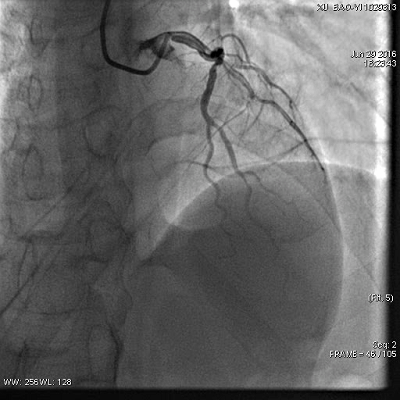

◆冠脉造影结果

◆左主干未见斑块及狭窄,前降支近段可见斑块,狭窄约50-60%,中段分出第二对角支后完全闭塞,血流Timi0级,回旋支中段及远段斑块,狭窄约80-90%,血流Timi3级,右冠全程管壁不规则,斑块狭窄约30-40%。

冠脉造影(左冠)

罪犯血管:左前降支